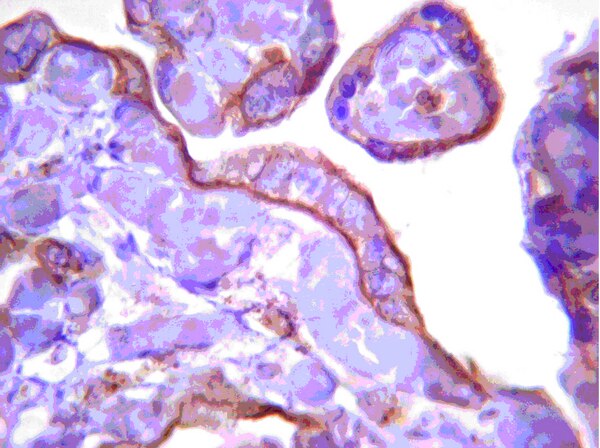

Malignant gliomas (MG), including grades III and IV astrocytomas, are the most common adult brain tumors. These tumors are highly aggressive with a median survival of less than 2 years. Nuclear factor I (NFI) is a family of transcription factors that regulates the expression of glial genes in the developing brain. We have previously shown that regulation of the brain fatty acid-binding protein (B-FABP; FABP7) and glial fibrillary acidic protein (GFAP) genes in MG cells is dependent on the phosphorylation state of NFI, with hypophosphorylation of NFI correlating with GFAP and B-FABP expression. Importantly, NFI phosphorylation is dependent on phosphatase activity that is enriched in GFAP/B-FABP+ve cells. Using chromatin immunoprecipitation, we show that NFI occupies the GFAP and B-FABP promoters in NFI-hypophosphorylated GFAP/B-FABP+ve MG cells. NFI occupancy, NFI-dependent transcriptional activity, and NFI phosphorylation are all modulated by the serine/threonine phosphatase calcineurin. Importantly, a cleaved form of calcineurin, associated with increased phosphatase activity, is specifically expressed in NFI-hypophosphorylated GFAP/B-FABP+ve MG cells. Calcineurin in GFAP/B-FABP+ve MG cells localizes to the nucleus. In contrast, calcineurin is primarily found in the cytoplasm of GFAP/B-FABP-ve cells, suggesting a dual mechanism for calcineurin activation in MG. Finally, our results demonstrate that calcineurin expression is up-regulated in areas of high infiltration/migration in grade IV astrocytoma tumor tissue. Our data suggest a critical role for calcineurin in NFI transcriptional regulation and in the determination of MG infiltrative properties. | Western Blotting | 23839947